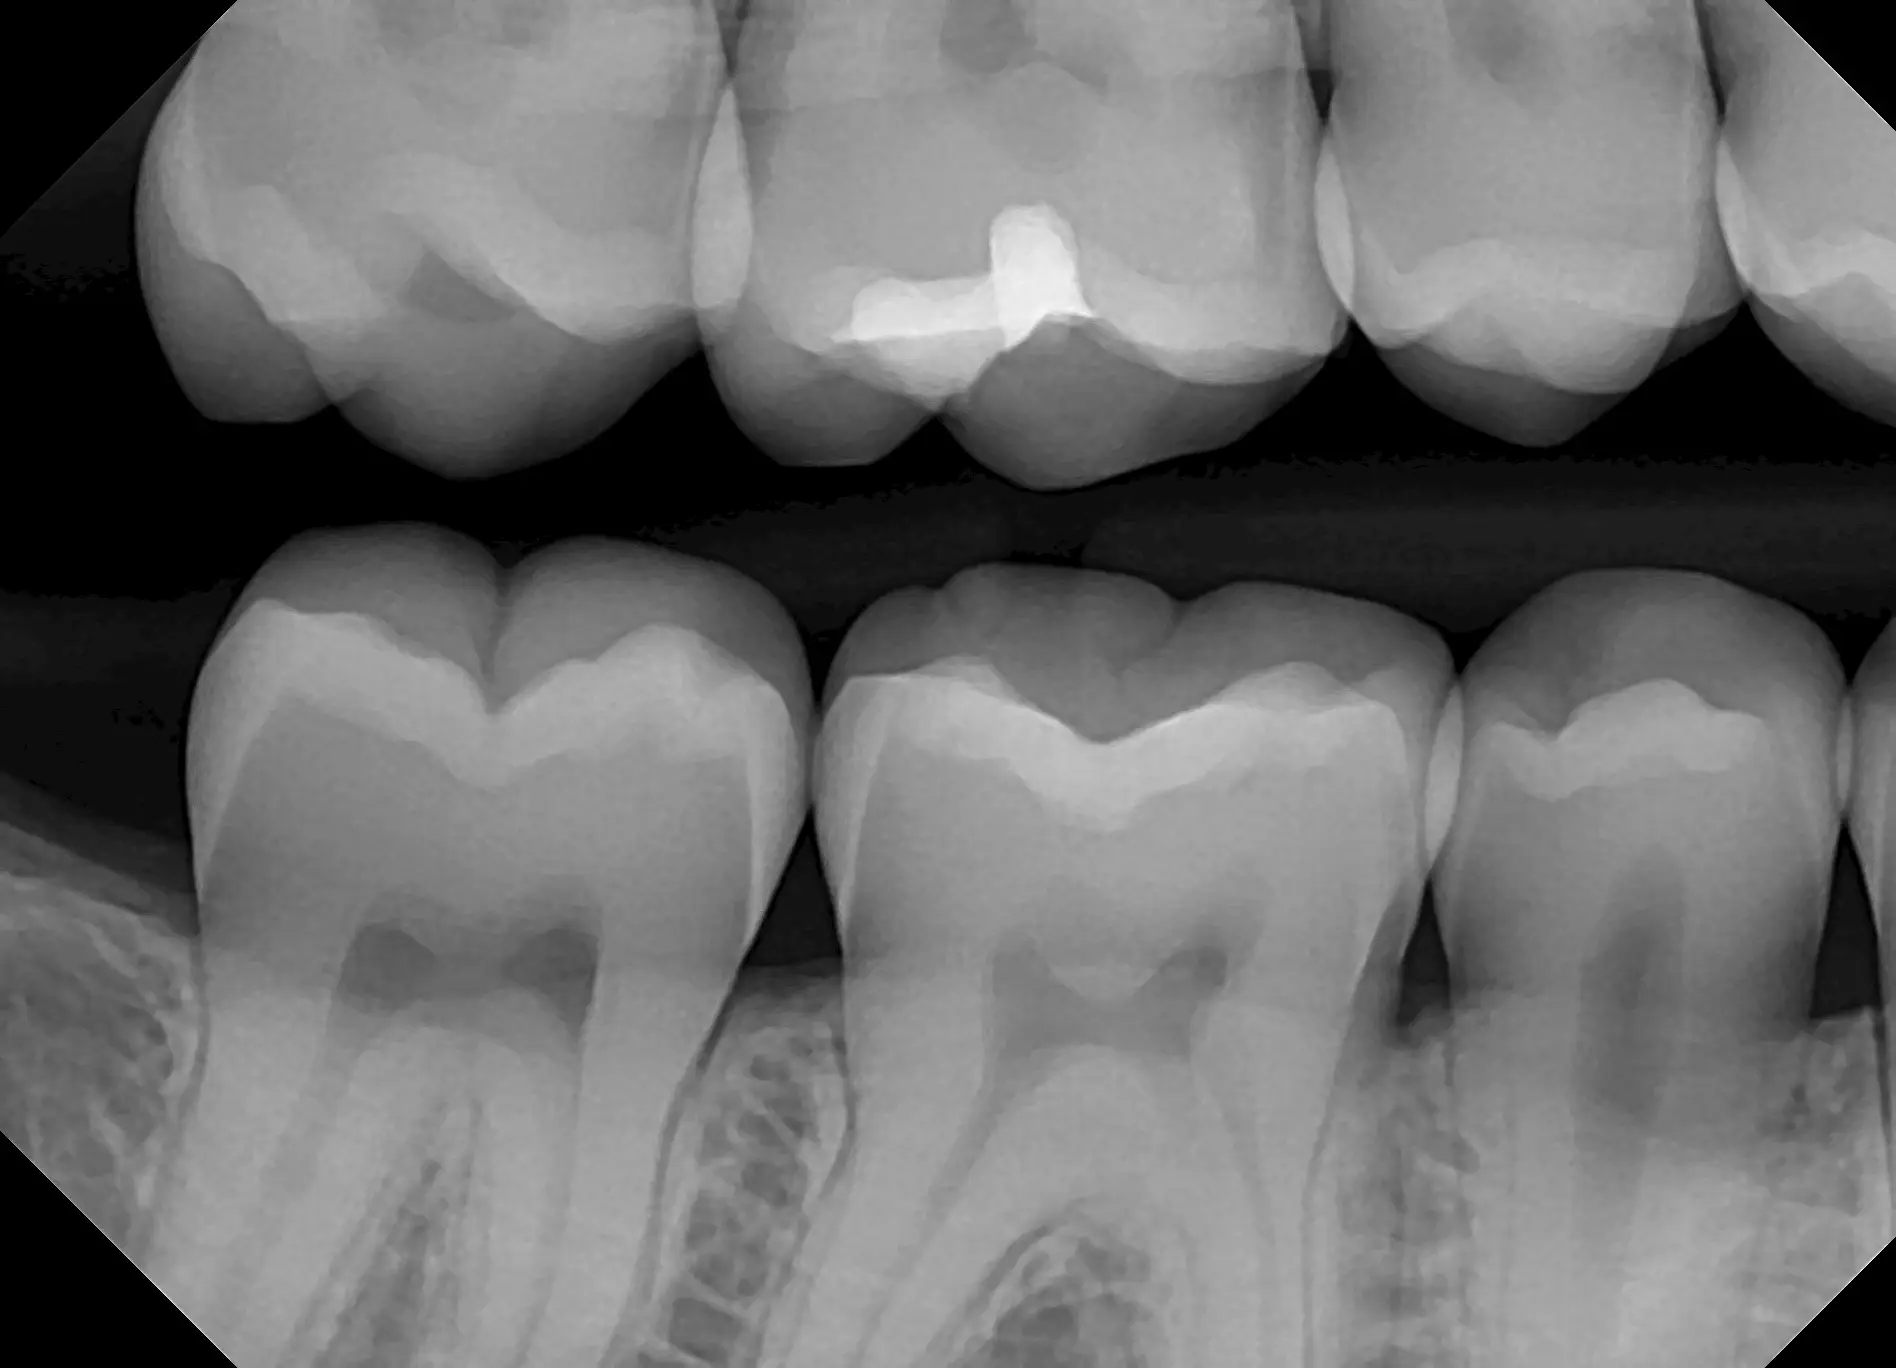

See for yourself the X-ray Gallery from the Dream Sensor!

Click any image in the x-ray gallery below to see the full version.

All images are taken with the DentiMax Dream Sensor and are compatible with the DentiMax Imaging Software and most other imaging software on the market.